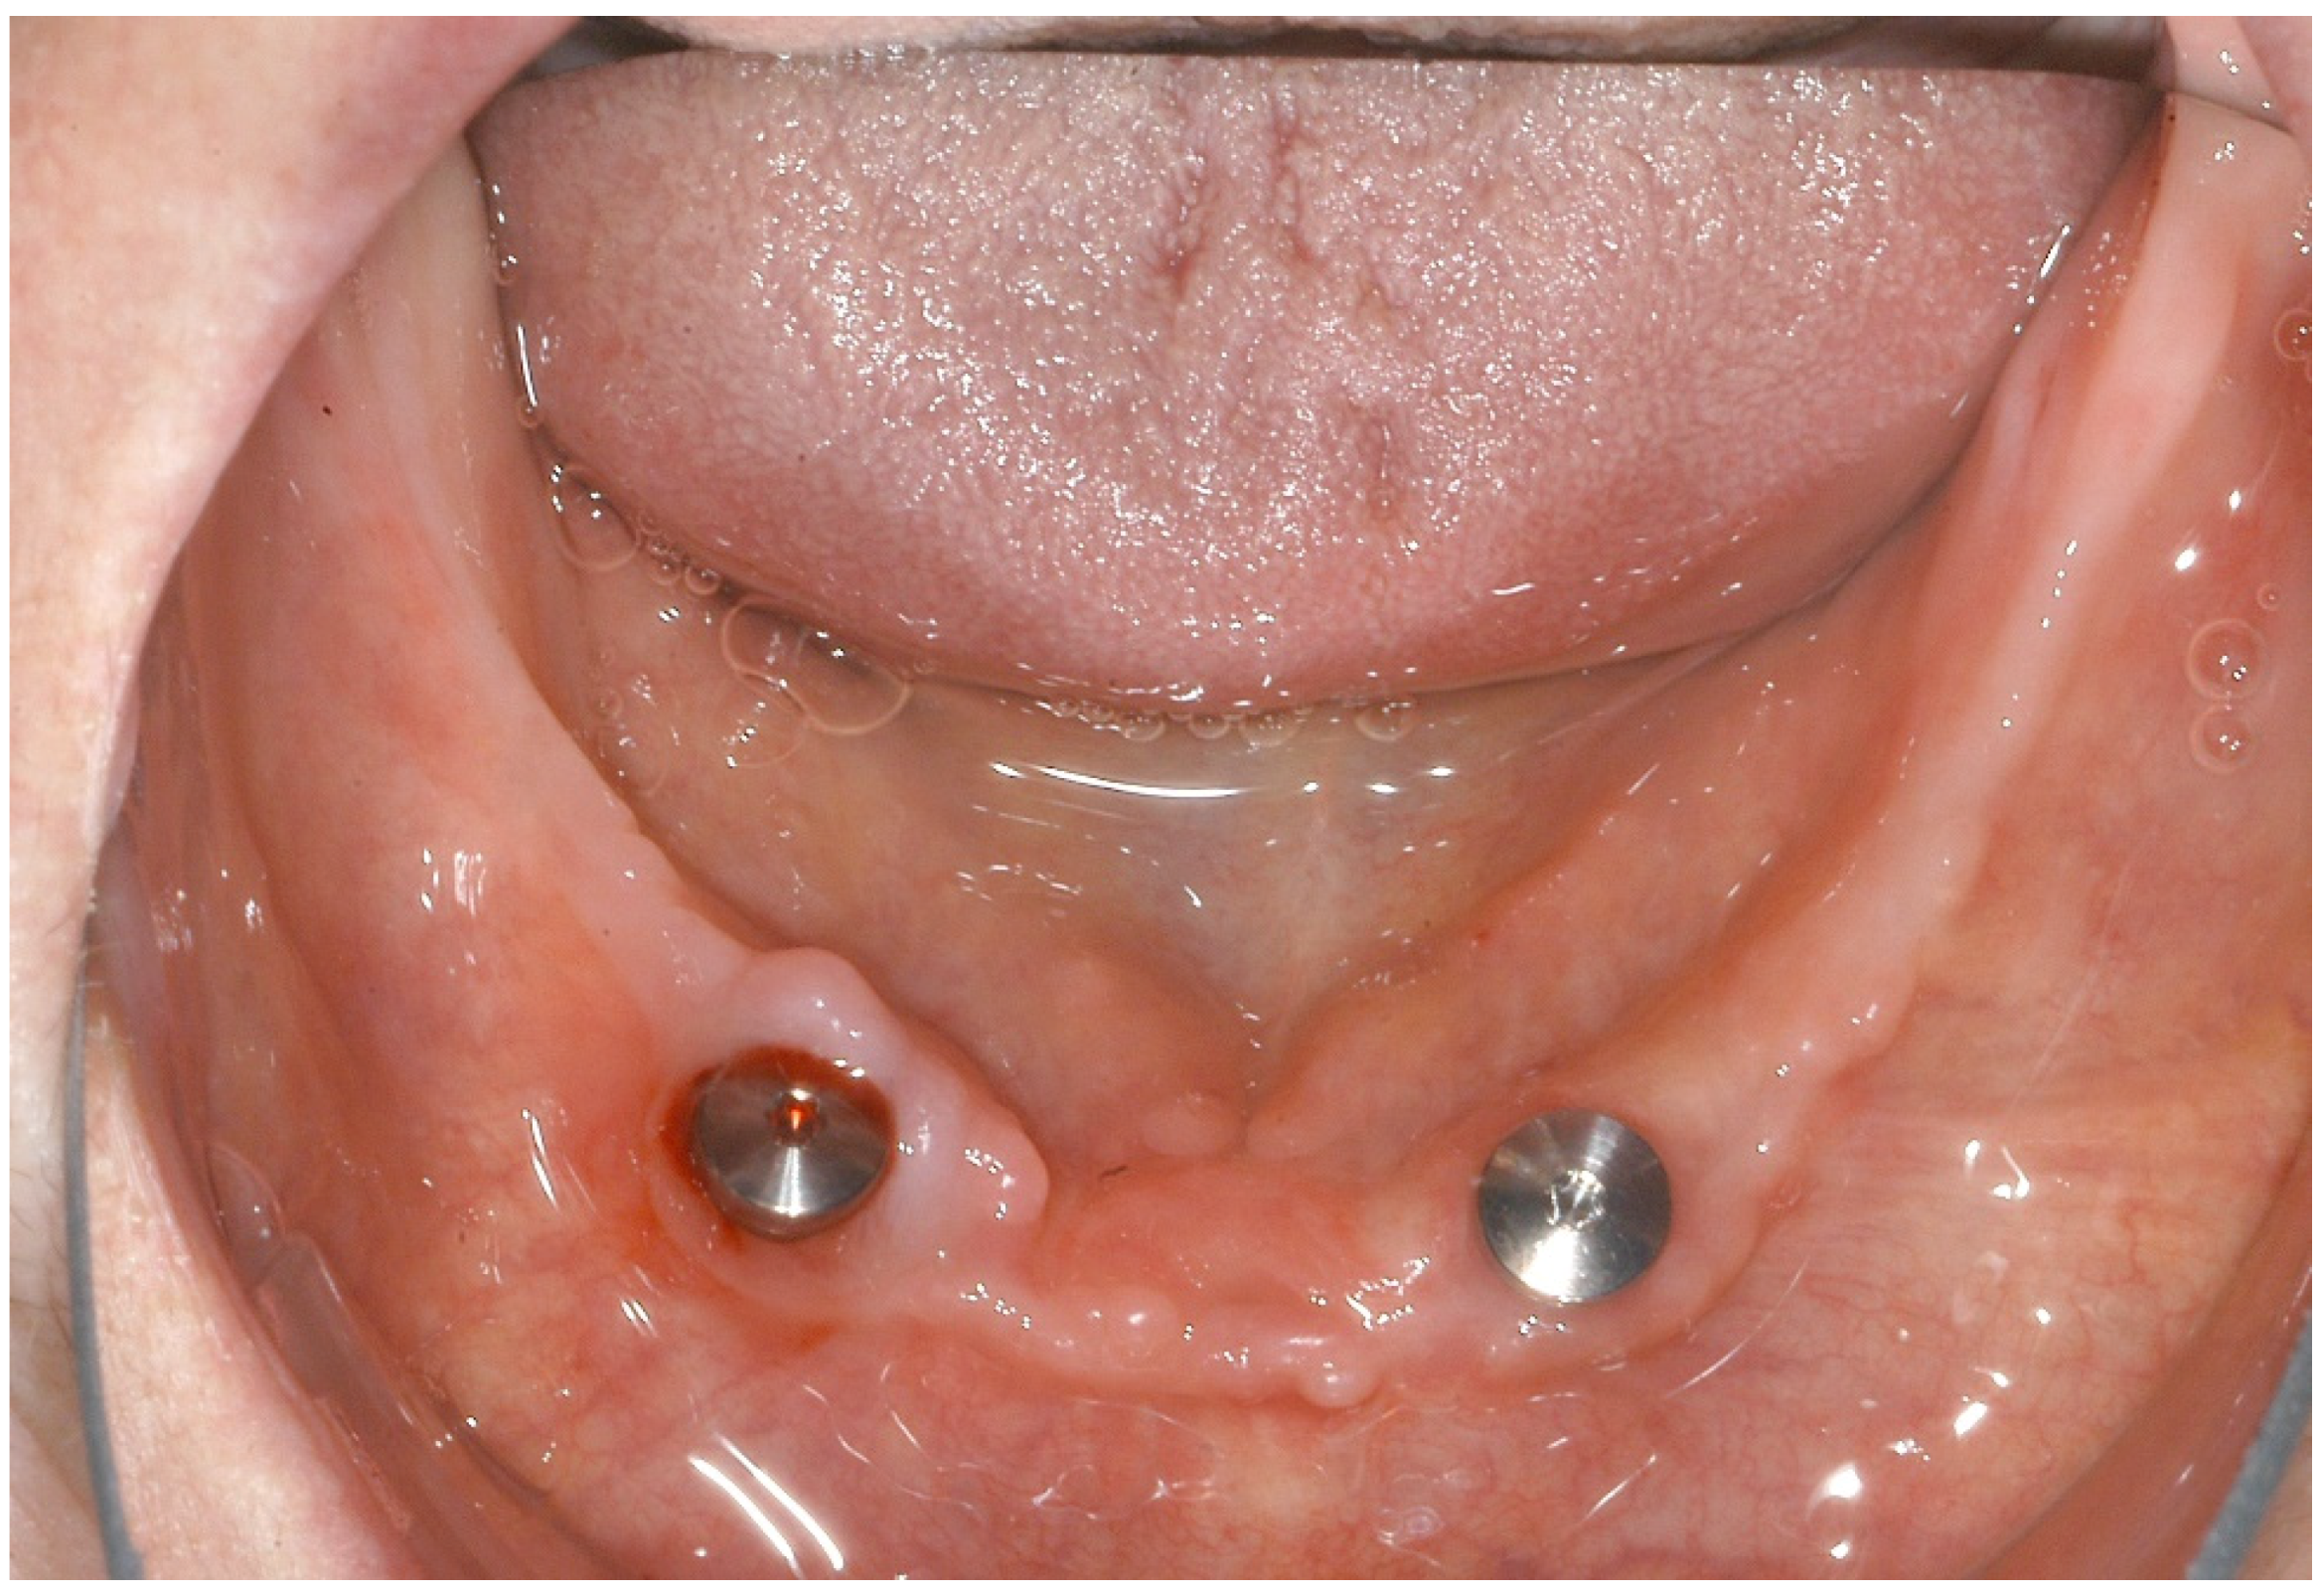

2. Case Report